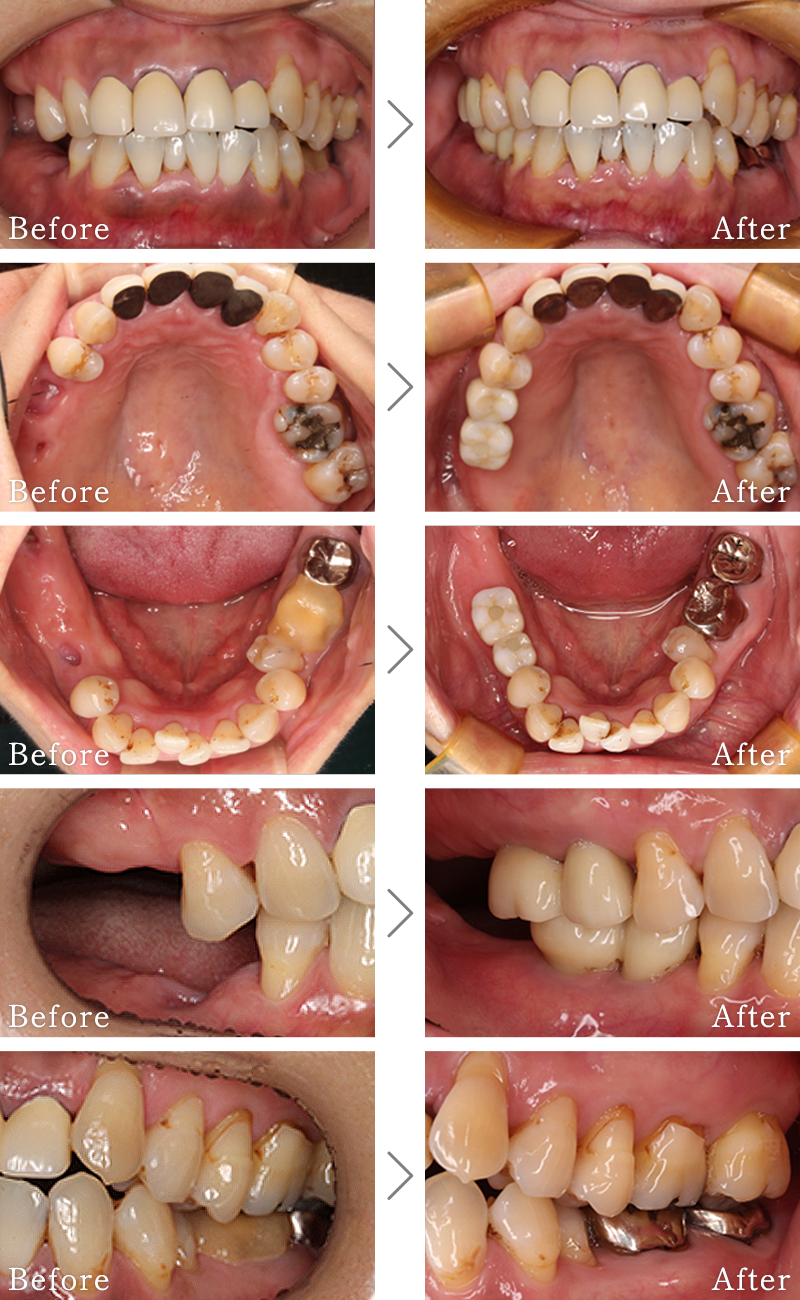

CASE2

主訴 奥歯でしっかりと噛むことができない、入れ歯もすぐに壊れてしまうとのことで来院されました。

治療法 下の奥歯を右1本、左2本のインプラントとセラミックの被せ物で噛み合わせを回復しています。

治療期間 4ヶ月

費用 CT:16,500円(税込)

+ インプラント治療:1,577,400円(税込)

合計:1,593,900円(税込)

CASE3

主訴 入れ歯も合わず、しっかりと噛んで食事ができないとのことで来院されました。

治療法 上下ともにALL-ON-6と呼ばれる最少本数のインプラントで全ての歯を回復する治療を行なっています。歯の部分は全てセラミックで作成されています。

治療期間 10ヶ月

※矯正治療の期間は含まれておりません。

+ インプラント治療:1,051,600円(税込)

+ 造骨処置(GBR):176,000円(税込)

合計:1,244,100円(税込)

※矯正治療費は含まれておりません。

CASE4

主訴 右の奥歯は無くなって食事が噛めない。

治療法 上下2本ずつインプラントを使用して噛み合わせを回復させています。

+ 静脈内鎮静法:66,000円(税込)

+ インプラント治療:2,103,200円(税込)

合計:2,185,700円(税込)